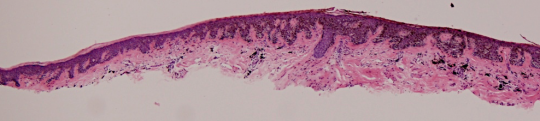

VA200: Left Upper Arm, Combined Nevus